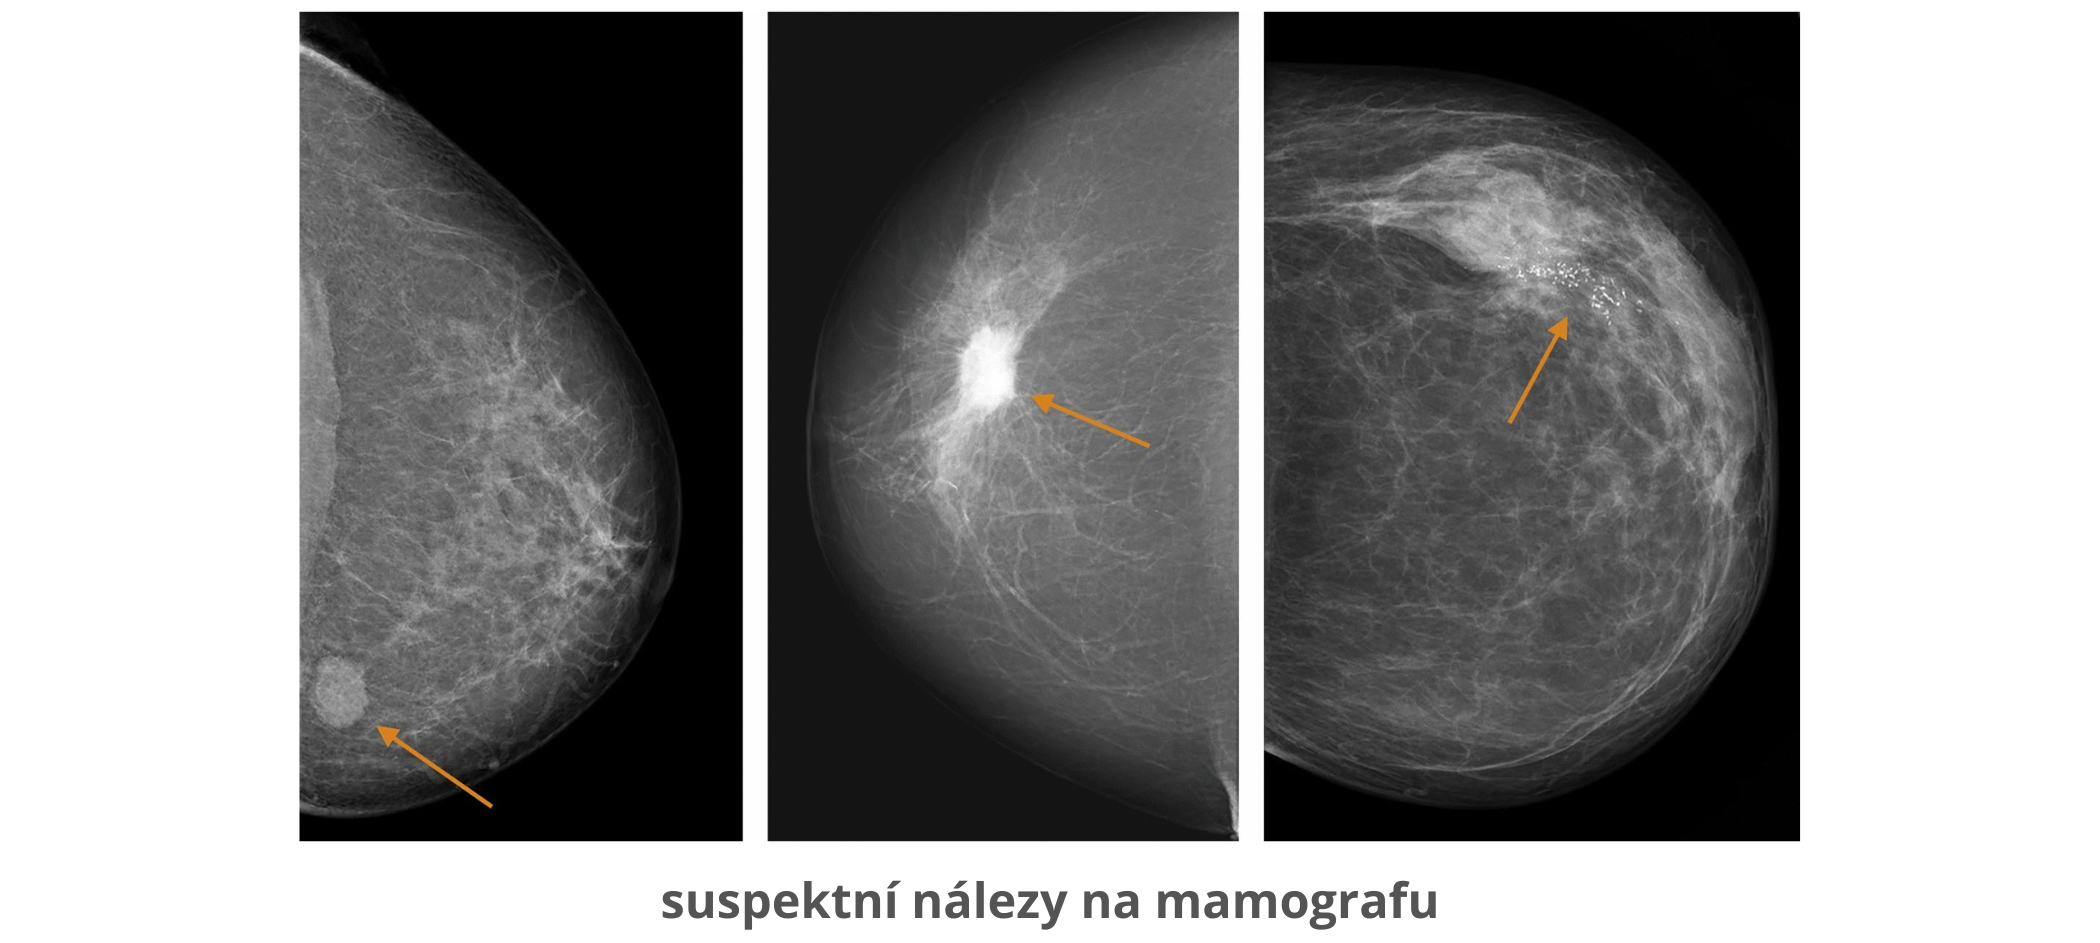

Mamografie

Mamografie je radiologická metoda vyšetřování prsu (rentgenové vyšetření). Využívá rentgenové paprsky k vytvoření obrazů vnitřních struktur těla. Na snímcích se hodnotí řada detailů, které mohou napovědět, zda se jedná o normální nález, nebo o něco, co vyžaduje další vyšetření:

Mikrokalcifikace – drobné bílé tečky, které mohou být projevem neškodných změn, ale také jedním z prvních znaků karcinomu.

Ložiskové útvary – na snímku se zobrazují jako stíny či zhuštěná oblast tkáně. Důležitý je jejich tvar a okraje – pravidelný, hladký útvar většinou značí benigní proces, nepravidelné a hvězdicovité okraje spíše budí podezření.

Asymetrie – porovnává se pravý a levý prs, případně aktuální snímek s těmi staršími. Nově vzniklá odchylka je vždy důvodem k bližšímu zkoumání.

Digitální mamografie dnes umožňuje obraz zvětšit, zvýraznit nebo přímo porovnat s předchozími snímky. Díky tomu je možné zachytit i milimetrové změny, které by jinak zůstaly skryté.